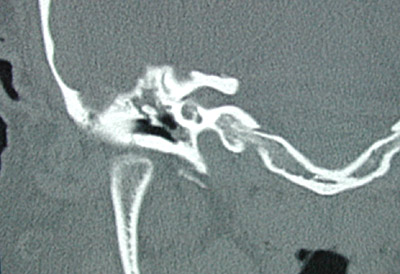

| The axial CT scan view of the head on the right seen above reveals a soft tissue density within the middle ear cavity that was associated with thickening and retraction of the tympanic membrane and abnormal soft tissue in the epitympanum with extension superiorly. A closer view is seen below. |